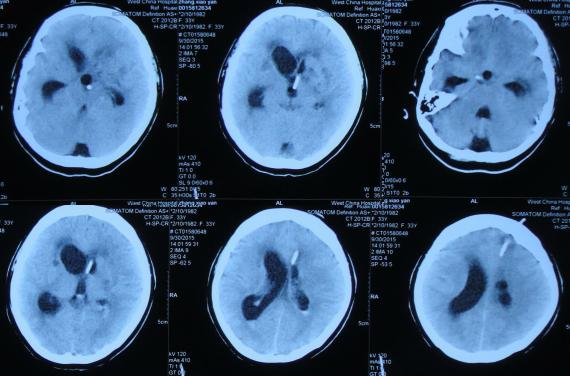

在第2家医院继续腰大池持续引流治疗1个月期间,曾多次查头部CT:2015年10月21日(图-15),2015年10月26日(图-16),2015年11月13日(图-17)均示脑室扩张反而越来越重。

图-15:2015年10月21日头部CT

图-16:2015年10月26日头部CT

图-17:2015年11月13日头部CT

第3家医院治疗31天

在第2家医院77天后即2015年11月20日,因患者意识呈昏睡状态,右侧肢体活动变更差,考虑结核可能更大,故转至第3家北京解放军某医院的结核科,入院时查PPD试验阳性,头部MRI示脑室扩张(图-18),给予异烟肼、利福平、乙胺丁醇,吡秦酰胺四联抗结核治疗,同时给予激素、营养支持治疗。

图-18:2015年11月20日头部MRI

第3家医院结核科治疗10天后即2015年11月30日,因脑室扩张加重,转至该院的神经外院,考虑双侧脑室不通,转入神外第2天即2015年12月2日接受了双侧脑室腹腔分流术及小脑病变活检术,术后当天查头部CT示双侧脑室分流术后状态(图-19)。

图-19:2015年12月2日头部CT

术后小脑病变病理示小脑组织内淋巴细胞浸润,见大量凝固性坏死,抗酸染色查到少量阳性菌,结核可能性大,继续给予异烟肼、利福平、乙胺丁醇,吡秦酰胺四联抗结核治疗,同时给予激素、营养支持治疗。

第3家医院治疗20天后即2015年12月10日,查头部CT示脑室仍有扩张(图-20)。

图-20:2015年12月10日头部CT